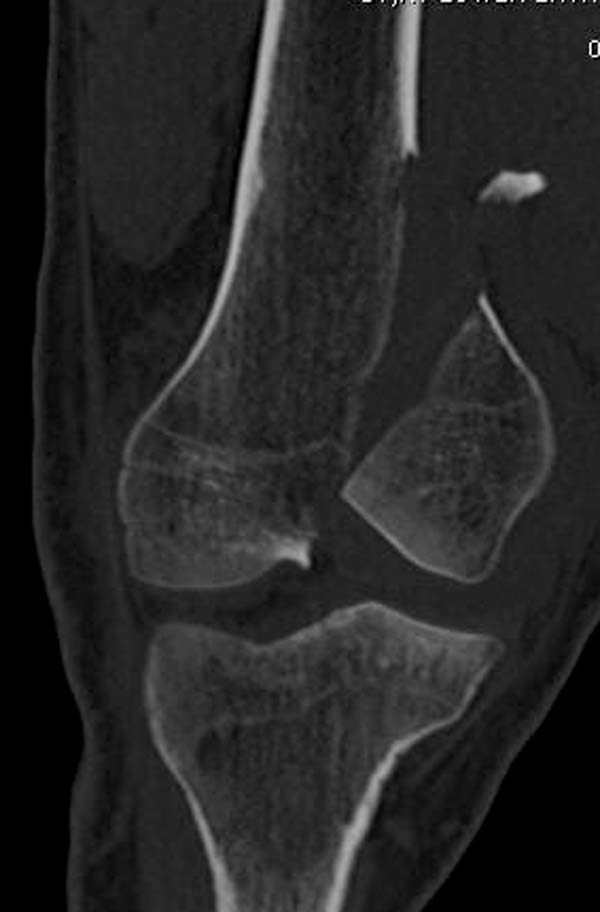

“Перелом наружного мыщелка правого бедра во фрональной плоскости был не замечен”

Диагностическая ошибка происходит, когда игнорируется правила обследования внутрисуставных переломов. Вместо полного обследования, включая КТ, ограничиваются рентгенограммой, и то в одной проекции!

Nork et al, J Orthop Trauma, 87:564, 2005 доложили, что над- и чрезмыщелковые переломы бедра в 38% имеют линию перелома в корональной плоскости!

Спасибо большое за советы! Добавляю некоторые КТ снимки. Перелом коллеги не диагностировали, видимо, расценив костную травму как повреждение задне-латерального комплекса коленного сустава. Отпишусь по результату выполненной операции.